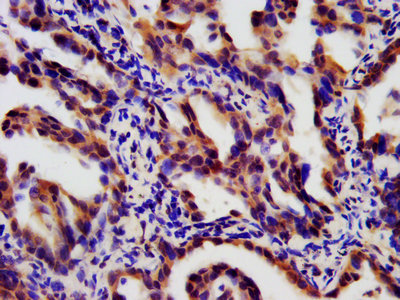

IHC image of CSB-PA08129A0Rb diluted at 1:180 and staining in paraffin-embedded human lung cancer performed on a Leica BondTM system. After dewaxing and hydration, antigen retrieval was mediated by high pressure in a citrate buffer (pH 6.0). Section was blocked with 10% normal goat serum 30min at RT. Then primary antibody (1% BSA) was incubated at 4°C overnight. The primary is detected by a biotinylated secondary antibody and visualized using an HRP conjugated SP system.